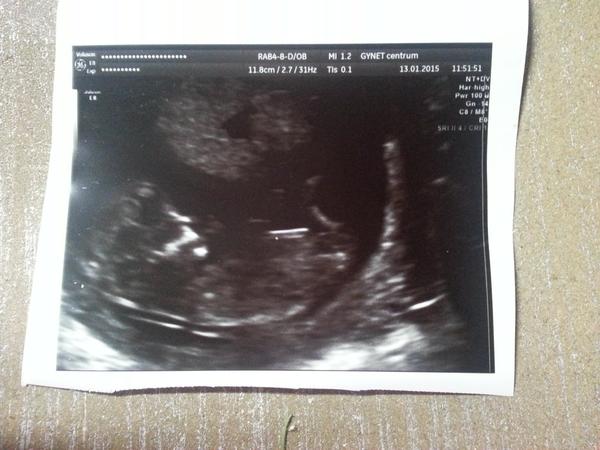

@nikcza To je skoro jak ta má fotka z utz a je to chlapeček tak třeba to bude ten kluk ale to je fakt těžko říct takhle.. 😀